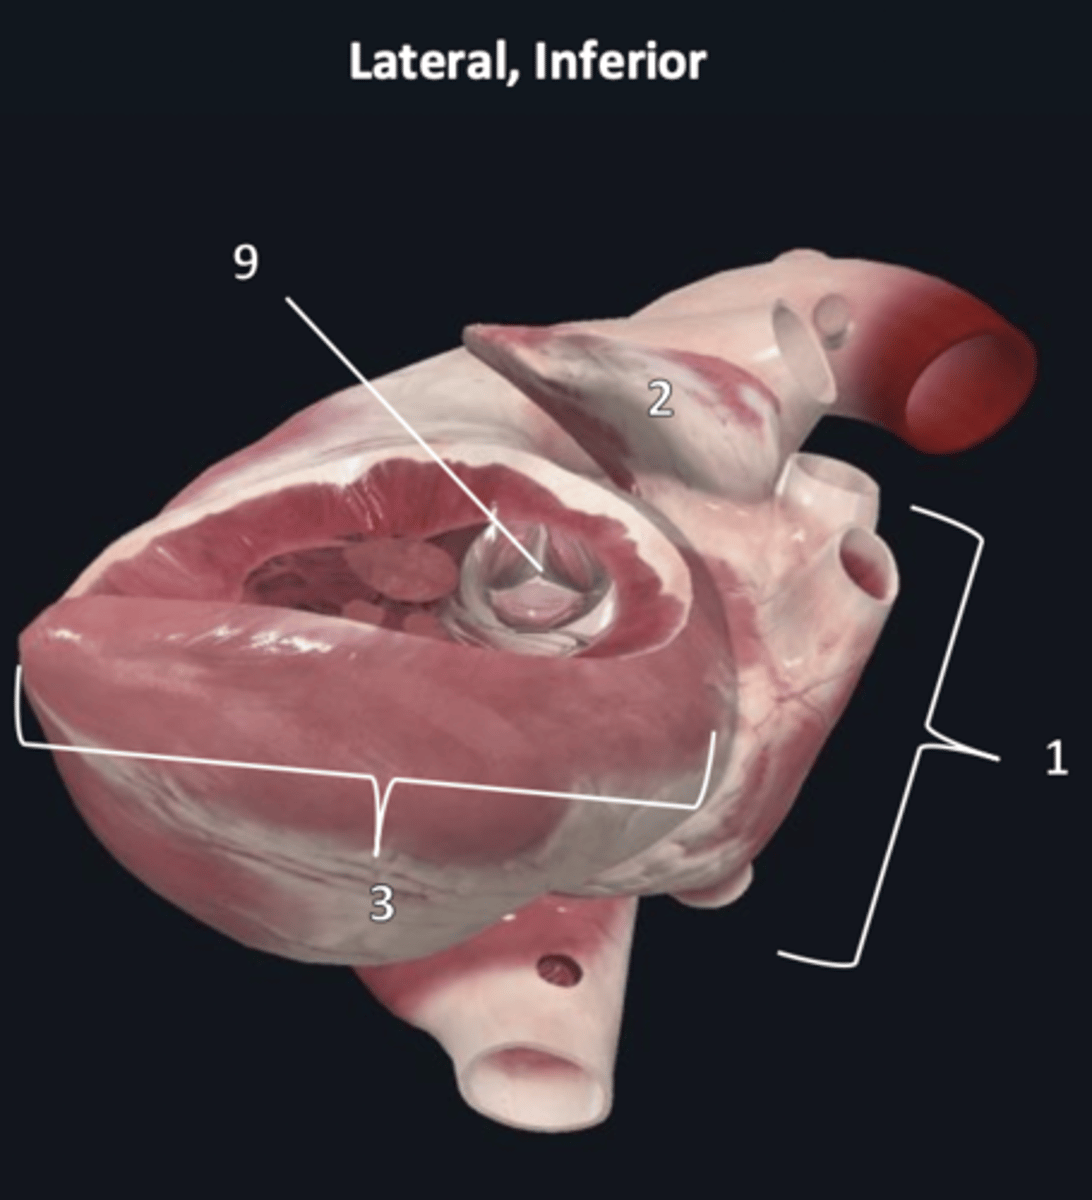

right ventricle

1

trabeculae carneae

2

septal papillary muscle

3

anterior papillary muscle

4

inferior papillary muscle

5

chordae tendineae

6

moderator band

7

tricuspid valve

8

pulmonary semilunar valve

9

interventricular septum

10